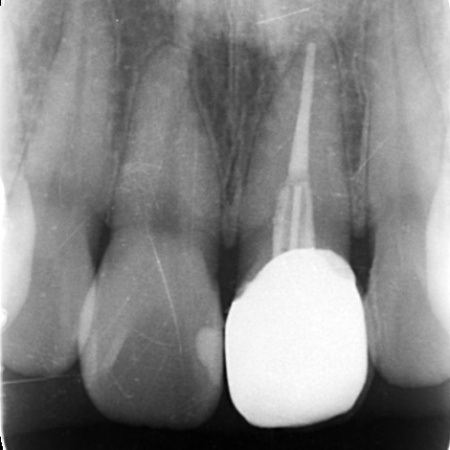

お口の中を拝見したところ、左上の前歯が大きく折れて被せ物を支える土台ごと外れていました。

レントゲン検査で確認した結果、歯の根自体には問題がなく炎症も見られなかったため、適切な治療を行えば歯を残せる状態であることが判明しました。

そこで、白いグラスファイバーを用いた土台(ファイバーコア)に白い被せ物(ジルコニアセラミッククラウン)を装着する治療を提案し、同意いただきました。

ファイバーコアと接着剤を組み合わせることで歯根と一体化させ、丈夫で長持ちする土台に仕上げました。

土台が完成したあとは歯科用顕微鏡のマイクロスコープで確認しながら、被せ物をスムーズに装着できるよう歯の形を丁寧に整えました。

後日、完成したジルコニアセラミッククラウンを装着し、治療を完了しました。